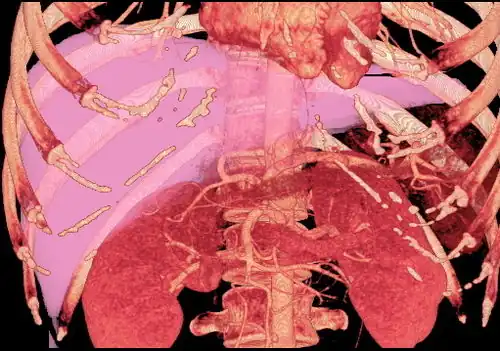

Technique

Before transplantation, liver-support therapy might be indicated (bridging-to-transplantation). Artificial liver support, like liver dialysis or bioartificial liver support concepts, is currently under preclinical and clinical evaluation. Virtually all liver transplants are done in an orthotopic fashion; that is, the native liver is removed and the new liver is placed in the same anatomic location.[10] The transplant operation can be conceptualized as consisting of the hepatectomy (liver removal) phase, the anhepatic (no liver) phase, and the postimplantation phase. The operation is done through a large incision in the upper abdomen. The hepatectomy involves division of all ligamentous attachments to the liver, as well as the common bile duct, hepatic artery, all three hepatic veins and portal vein. Usually, the retrohepatic portion of the inferior vena cava is removed along with the liver, although an alternative technique preserves the recipient's vena cava ("piggyback" technique).

The donor's blood in the liver will be replaced by an ice-cold organ storage solution, such as UW (Viaspan) or HTK, until the allograft liver is implanted. Implantation involves anastomoses (connections) of the inferior vena cava, portal vein, and hepatic artery. After blood flow is restored to the new liver, the biliary (bile duct) anastomosis is constructed, either to the recipient's own bile duct or to the small intestine. The surgery usually takes between five and six hours, but may be longer or shorter due to the difficulty of the operation and the experience of the surgeon.

The vast majority of liver transplants use the entire liver from a non-living donor for the transplant, particularly for adult recipients. A major advance in pediatric liver transplantation was the development of reduced-size liver transplantation, in which a portion of an adult liver is used for an infant or small child. Further developments in this area included split liver transplantation, in which one liver is used for transplants for two recipients, and living donor liver transplantation, in which a portion of a healthy person's liver is removed and used as the allograft. Living donor liver transplantation for pediatric recipients involves removal of approximately 20% of the liver (Couinaud segments 2 and 3).